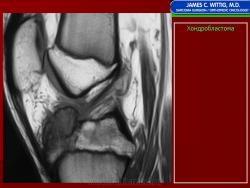

Хондробластома — это редкая доброкачественная опухоль, локализующаяся, главным образом, в эпифизе и отличающаяся своеобразным клеточным составом. Ткань новообразования представлена овальными, округлыми и веретеновидными клетками, напоминающими незрелые хондроциты (хондробласты). Зрелый гиалиновый хрящ определяется лишь в некоторых опухолях. Возраст больных варьирует. Мужчины поражаются в два раза чаше женщин. Пациенты предъявляют жалобы на боли в течение нескольких месяцев или лет, у некоторых больных определяются внутрисуставной выпот, припухлость и ограничение движений. Наиболее типичная локализация опухоли — проксимальные эпифизы плечевой и большеберцовой костей, а также дистальный эпифиз бедренной кости. У 20 % больных опухоль развивается в плоских или коротких трубчатых костях, преимущественно в пяточной и таранной. Изредка поражаются кости лицевого черепа, в том числе височная. В большинстве случаев новообразование выходит за пределы эпифиза и распространяется на метафиз. На фоне остеолиза обнаруживаются рассеянные участки обызвествления в виде пунктирных линий, а также разреженный трабекулярный рисунок. Хондробластома, как правило, не выходит за пределы кости, но изредка проникает в полость сустава. В процессе роста опухоли иногда возникает вторичная аневризматическая костная киста.

Рентгенологически хондробластома представляет собой сравнительно большой (2-4 см) очаг округлой формы, четко отграниченный от окружающей кости склеротической каймой. На фоне очага в большинстве случаев, но не обязательно определяются плотные включения, напоминающие хлопья ваты.

Рентгенологическая картина. Хондробластома выглядит как небольшой, от 3 до 6 см литический очаг, центрально или эксцентрично расположенный, с четкими контурами, занимающий около половины площади эпифизарной зоны. Хондробластома плоских костей и мелких трубчатых костей больших размеров, может сопровождаться припухлостью мягких тканей, вздутием кости и периостальной реакцией. Распространение процесса на метафизарную зону встречается часто.